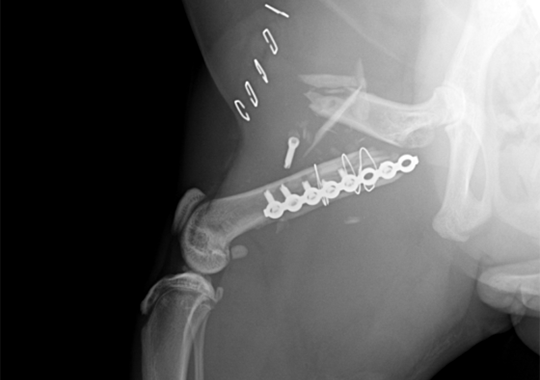

대퇴골 복합골절 및 천장골분리골절 전

대퇴골 복합골절 및 천장골분리골절 후

정형외과 케이스

본원은 실력 있는 전문 의료진과 최첨단 시설로 정형외과에서 좋은 예후들을 보여드리고 있습니다. 강아지에게서 쉽게 발생하는 슬개골 탈구, 십자인대 단열 뿐 아니라 다양한 고난도 케이스를 다루고 있으며, 특히 골절 수술은 회복률이 높고 타원 수술 후, 유합부전으로 본원에 내원하여 재수술에 성공한 사례가 많습니다.